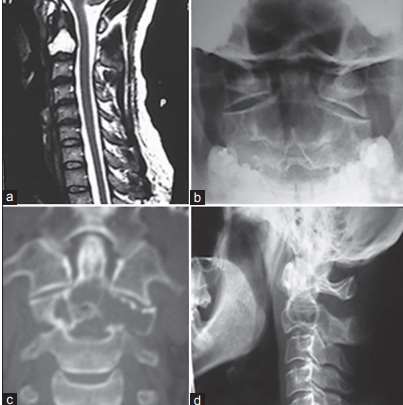

Cistos degenerativos intraósseos(CDI) da espinha cervical são raros. CDIs dentro de C2 foram reportados em apenas 3 artigos. Nós ilustramos um paciente com dor no pescoço devido a um CDI dentro da segunda vértebra. Discutimos o diagnóstico diferencial das lesões e as abordagens cirúrgicas para alcançar essa região anatômica complexa.

Por Dr. Gustavo Rassier Isolan, MD PhD.